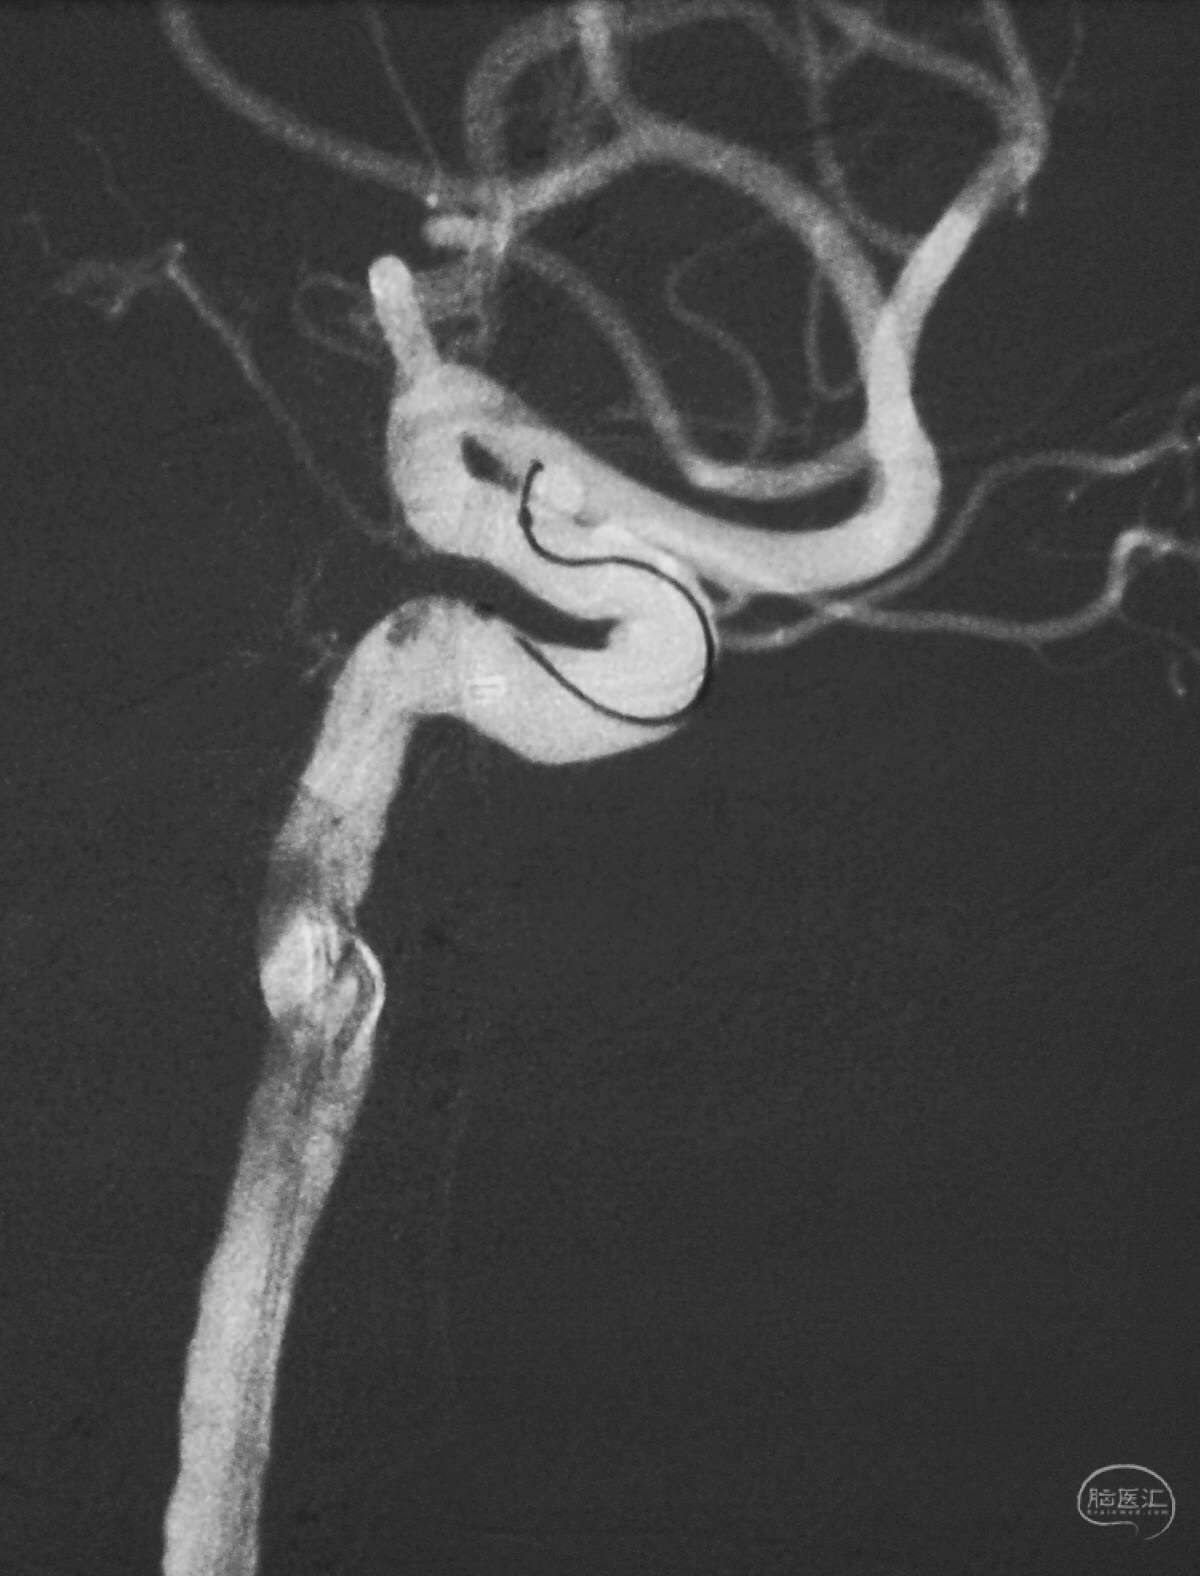

Solitaire 4×15支架(绿线)跨瘤颈半释放,压住微导管(红线)。

经微导管向瘤腔内送入首枚弹簧圈(QC-2-4-3D)。

继续送入两枚QC-1.5-2-Helix,完全栓塞动脉瘤,部分圈突入载瘤动脉。